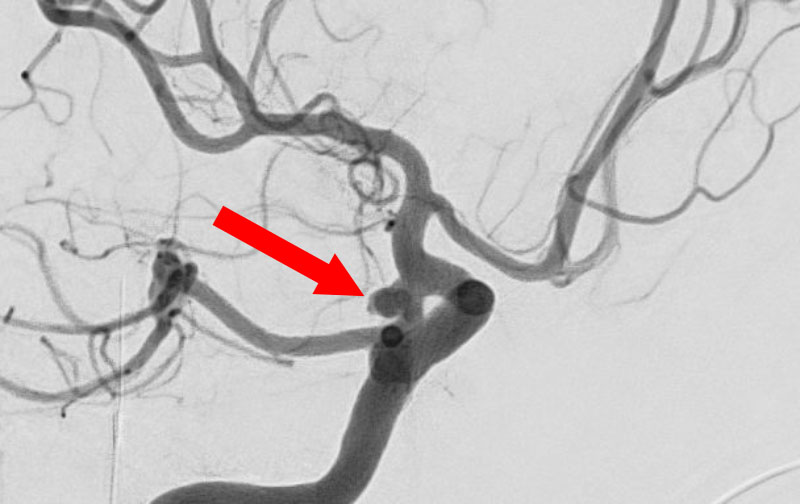

No.1631 手術前